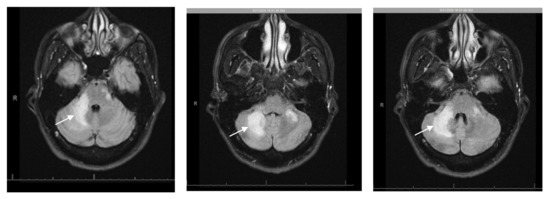

Two months after the initial presentation and despite compliance to ART, the patient was re-admitted for progressive neurological complaints, including worsening ataxia, now unable to stand or walk without assistance. The physical exam was notable for right facial droop, decreased sensation over the right face, marked dysmetria with finger-to-nose testing, and dysdiadochokinesia. He had significant ataxic gait but full muscle strength and negative pronator drift or nuchal rigidity. Repeat CSF studies were unrevealing. Brain MRI was concerning for worsening of previous PML lesions with multifocal brainstem and cerebellar T2/FLAIR hyperintense lesions, new extensive leptomeningeal and perivascular enhancement, and mass effect (Figure 2). Repeat T- lymphocyte subsets/HIV studies at this time showed: CD4 cell count 252 cells/mm3 [7.94%], CD8 2430.4 cells/mm3, CD4/CD8 ratio 0.1 and plasma HIV viral load decreased to 106 copies/mL. In the setting of radiologic and clinical progression of disease with recently diagnosed AIDS and ART initiation 1 month prior, paradoxical cerebellar PML-IRIS was diagnosed. While ART was continued, he was also started on an adjunctive intravenous methylprednisolone course 1 g daily for 5 days, followed by an oral prednisone taper 60 mg per day, with taper over 6 weeks and close outpatient follow up. The patient was discharged after 5 days of hospital stay.

Figure 2. Repeat MRI brain 2 months after compliance with antiretroviral therapy (ART) showing interval worsening of multifocal brainstem and cerebellar T2/FLAIR hyperintense lesions with mass effect. New diffuse leptomeningeal and perivascular enhancement in the cerebellum (arrow), brachium ponti, pons, and left midbrain.